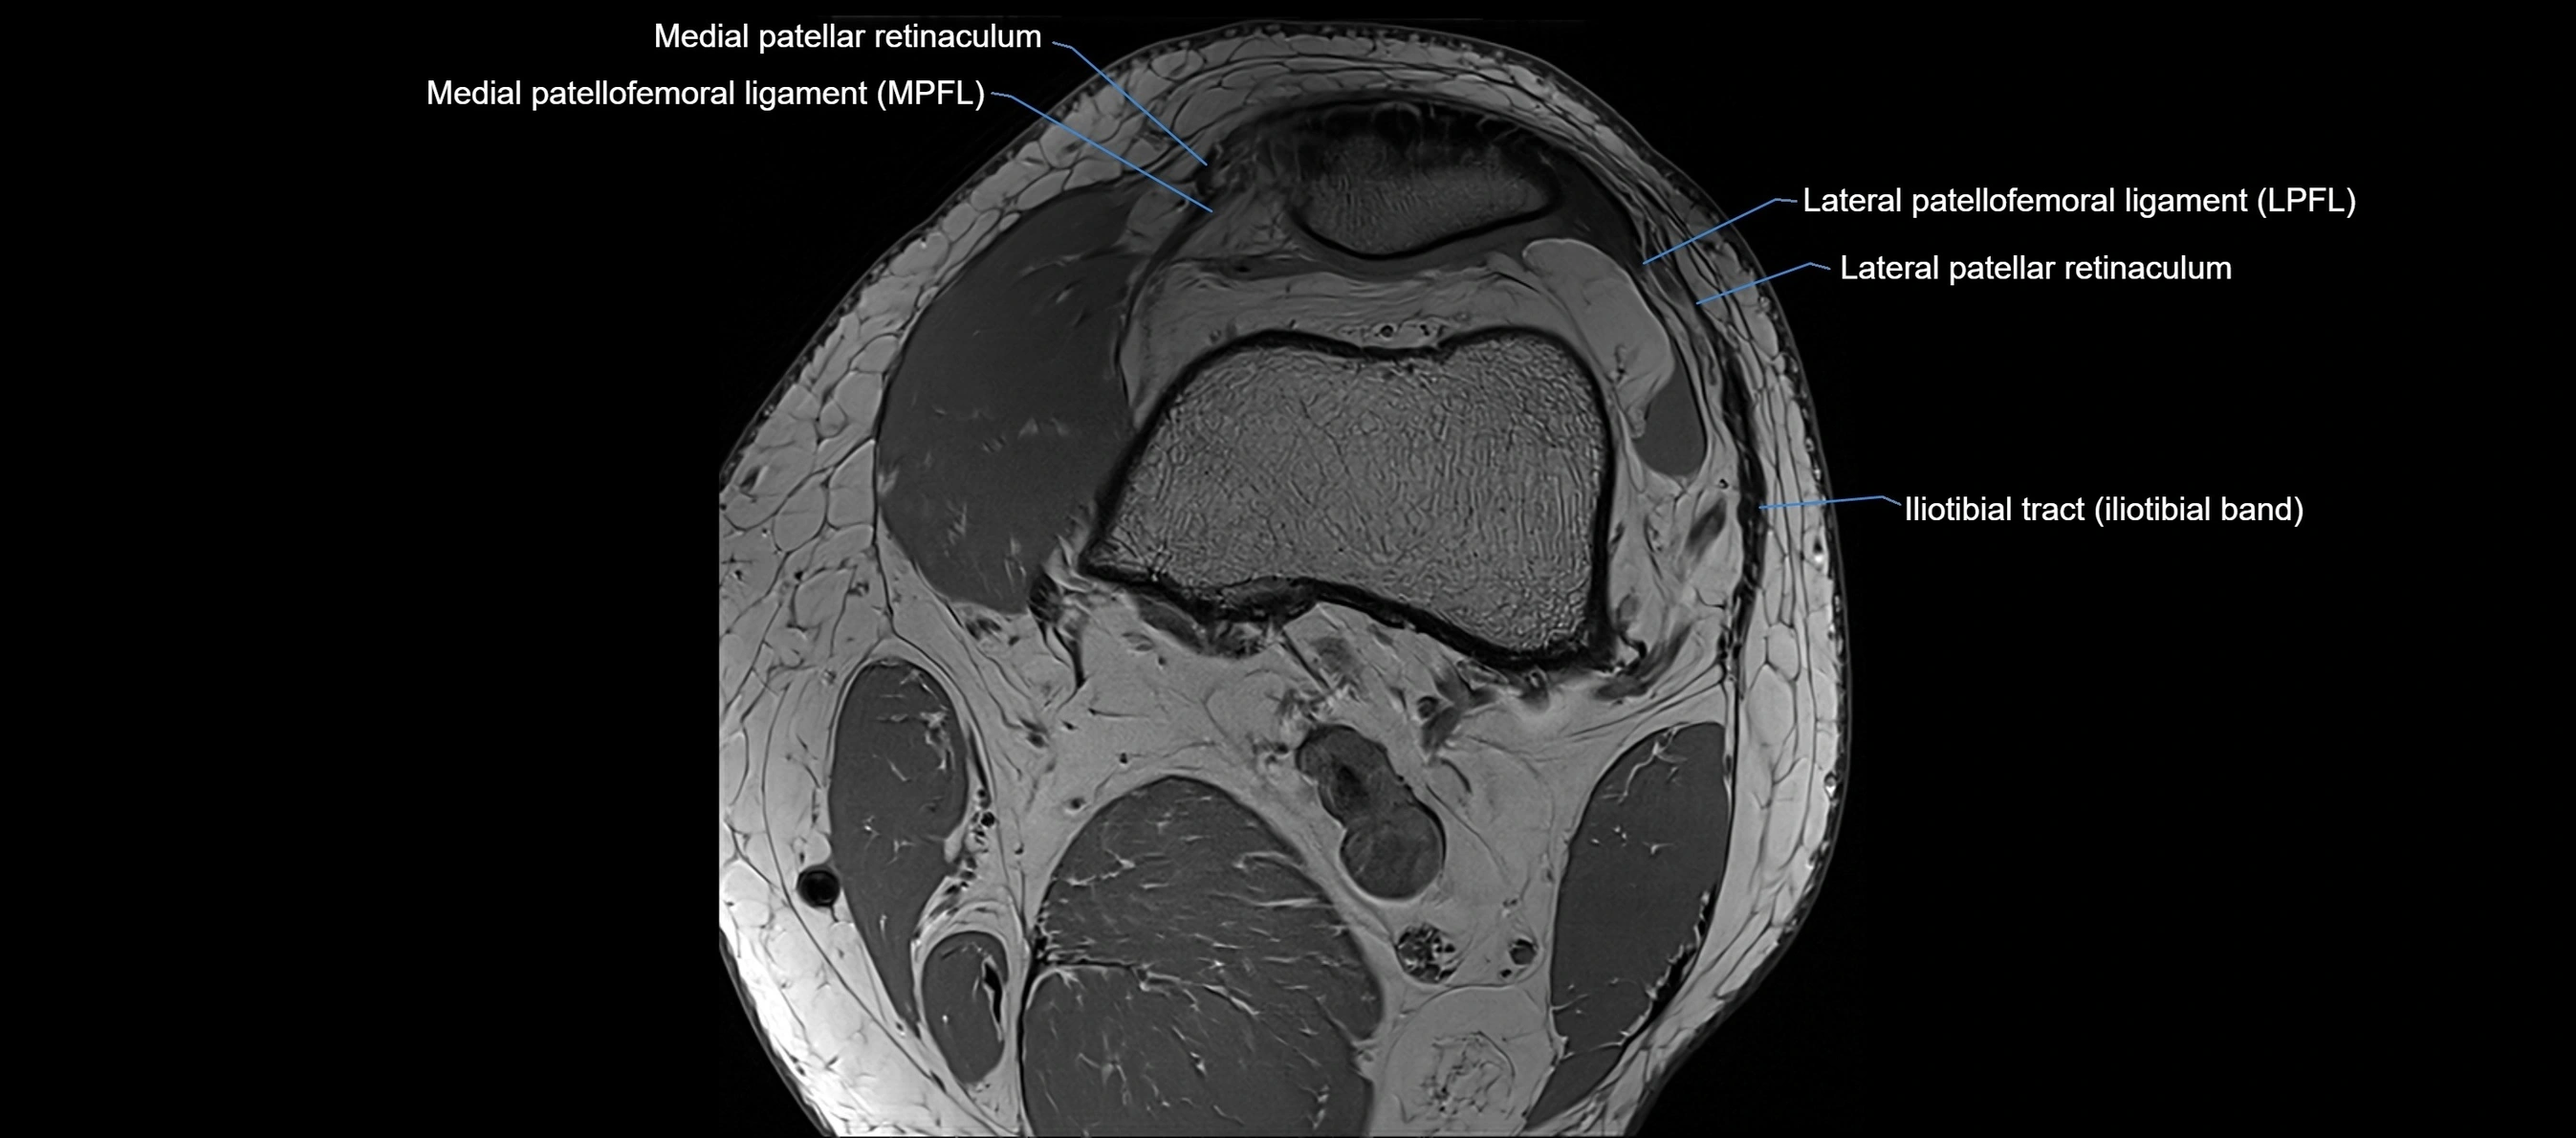

MRI images

image